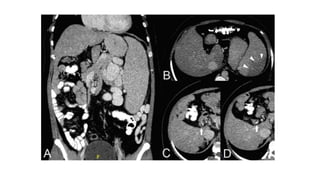

• #21 Axial and coronal contrast-enhanced Ct (A,B) a small liver with smooth margins and massive splenomegaly. Note the infarcts in the upper pole of spleen . But there is no ascites. (C,D) Hypodense filling defects and calcifications in the portal vein due to portal vein thrombosis.

• #22 CECT of the same patient in (A) shows a splenic artery aneurysm (arrowhead) from long-standing massive splenomegaly. (B) Portal vein thrombosis (arrowheads) and multiple dilated perigastric collaterals (arrow).

• #35 (CECT) axial shows hypoenhancement of the peripheral portions of the liver with a relatively increased enhancement in the caudate lobe (arrow), which is enlarged. There is ascites and nonvisualized hepatic veins.

• #37 (CECT) axial images with a markedly enlarged caudate lobe (arrow), irregular liver margins, and the presence of intrahepatic collaterals (arrow).